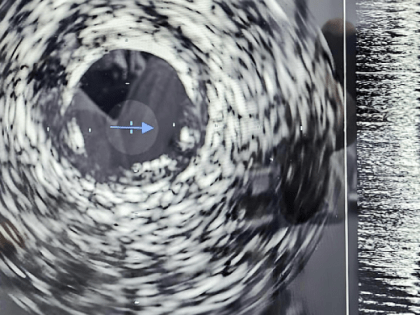

В Кирове начали применять внутрисосудистое ультразвуковое исследование

Кировская областная клиническая больница внедрила уникальную технологию, позволяет повысить качество стентирования при острой и хронической коронарной недостаточности.

В Кирове появилась новая техника для лечения болезней сердца

Фото правительства Кировской области О новой уникальной технологии внутрисосудистого ультразвукового исследования, которую теперь используют в Кировской областной клинической больнице  сообщили в  облправительстве.